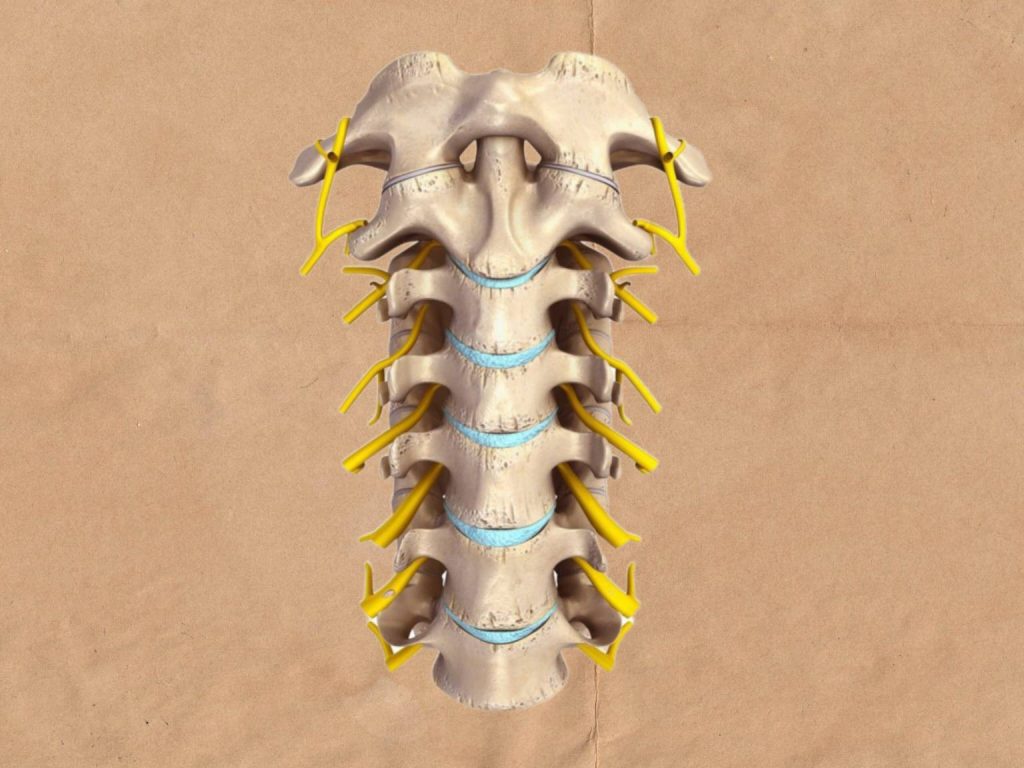

ستون فقرات

شامل 33 مهره است: 7مهره گردنی، 12 مهره پشتی، 5 مهره کمری، 5 مهره خاجی و 4 مهره دنبالچه. هر مهره از 2 بخش ساخته می شود شامل جسم مهره و قوس مهره در پشت. جسم و قوس مهره ای به گونه به یک دیگر متصل می شوند به طوری سوراخ مهره ای را تولید می کنند. سوراخ های بین مهره ای در کنار یک دیگر قرار می گیرند و مجرای نخاعی را می سازند. طناب نخاعی در مجرای نخاعی قرار دارد. بین جسم هر دو مهره یک دیسک قرار می گیرد. دیسک های بین مهره ای فشار را از روی ستون فقرات برمی دارند.

ستون فقرات محور مرکزی بدن را تشکیل می دهد و در پشت تنه و در خط وسط قرار دارد.

تنگی کانال نخاعی

یک بیماری که می تواند طناب نخاعی و ریشه های عصبی را درگیر کند. به باریک شدن فضایی بین ستون فقرات، تنگی کانال نخاعی گفته می شود. پس فضای موجود برای نخاع و اعصاب کاهش می یابد. این بیماری می تواند منجر به کمر درد و درد سیاتیک شود و به طور تدریجی ایجاد می شود. ممکن است در اثر آرتروز ایجاد شود و علامتی هم نداشته باشد. می تواند در هر نقطه ای از ستون فقرات ایجاد شود و در کمر و گردن شایع تر است.

علت های تنگی کانال نخاعی

علت های متفاوتی در ایجاد تنگی کانال نخاعی وجود دارد. از مهم ترین موارد می توان به رشد بیش از اندازه استخوانی یا زائده استخوانی اشاره کرد. رائده استخوانی وضعیتی است که منجر به تجزیه غضروف مفصل ها از جمله ستون فقرات می شود. با از بین رفتن غضروف استخوان ها روی یک دیگر ساییده می شوند. در این شرایط پاسخ بدن رشد استخوان نو است. به طوری که یک زائده استخوان شکل می گیرد. زائده استخوانی روی ستون فقرات رشد می کنند و فضا را باریک می کنند و اعصاب را تحت فشار قرار می دهند. به طوری که دیسک برآمده روی اعصاب فشار می آورد و فضای کانال نخاعی را کاهش می دهد.

علائم تنگی کانال نخاعی

در کمر به این صورت هست که یک درد کم یا سوزش حس می شود. این درد ممکن است ثابت نباشد. از علائم تنگی کانال نخاعی کمر می توان به این موارد اشاره کرد: درد سیاتیک به طوری که در پشت پا ها پایین رونده و تیرکشنده است، بی حسی و گزگز در باسن و پا ها، ضعف ساق پا ها، تشدید درد در سراشیبی و در موارد شدید از دست دادن کنترل مثانه و روده.

هم چنین علائم تنگی کانال نخاعی در گردن شامل گردن درد، بی حسی و گزگز بازو دست یا پا ها، ضعف بازو دست و پا ها، اختلالات تعادلی، از دست دادن عملکرد دست مانند مشکل نوشتن و از دست کنترل مثانه.

از عوارض شدید تنگی کانال نخاعی، فلج غیر قابل بازگشت است.

تشخیص و درمان تنگی کانال نخاعی

درمان تنگی کانال نخاعی به محل مشکل و شدت علائم بستگی دارد. در درمان اولیه می توانید از کمپرس گرم استفاده کنید. گرما جریان خون را افزایش می دهد و منجر به شل شدن عضلات و کاهش درد می شود. در هنگام استفاده از گرما مراقب باشید دچار سوختگی نشوید. اگر گرما پاسخ نداد از سرما و کمپرس یخ استفاده کنید. معمولا کمپرس سرد را تا 20 دقیقه روی ناحیه قرار می دهند و التهاب کاهش می یابد. یکی دیگر از درمان های مفید، ورزش های تنگی کانال نخاعی است. به طوری که به جهت حمایت از ستون فقرات و بهبود انعطاف پذیری و تعادل بسیار مناسب است.

دارو درمانی از دیگر روش های درمانی تنگی کانال نخاعی است که باید زیر نظر متخصص باشد. یکی از مهم ترین روش های درمانی فیزیوتراپی است. به طوری که به شما کمک می کند برنامه تمرینی صحیحی برای تعادل، انعطاف پذیری و ثبات ستون فقرات داشته باشید. این کار فشار را از روی ریشه های اعصاب برمی دارد. تزریق کورتیکواستروئید ها دیگر روش درمانی است. به طوری که در فضایی در نزدیکی ستون فقرات می تواند به کاهش درد، التهاب و تحریک کمک کند. با این حال امکان تزریق محدود است.

روش های جراحی تنگی کانال نخاعی شامل این موارد است:

لامینکتومی: در این روش قسمت لامینا استخوان آسیب دیده ستون فقرات برداشته می شود. این کار فضای بیشتری در اطراف اعصاب ایجاد می کند.

لامینوتومی: در این روش تنها قسمتی از لامینا برداشته می شود. جراح سوراخی را به اندازه کافی بزرگ می کند تا فشار را در یک نقطه کاهش بدهد.

لامینوپلاتی: ویژه استخوان ستون فقرات گردن است. مهم ترین خطر های آن، عفونت، لخته خون در پا ها و پارگی غشا نخاعی را می توان اشاره کرد.